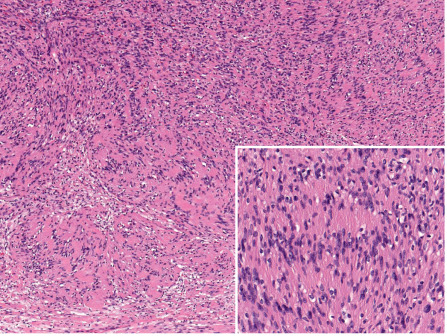

Schwannomas are well-circumscribed, nodular or ovoid tumors located in the deep dermis or subcutis. They are almost always encapsulated. The tumors are composed of hypercellular (also called Antoni A-type tissue) and hypocellular (Antoni B-type tissue) areas . The hypercellular areas show proliferation of spindle cells with indistinct cytoplasmic contours and uniform nuclei . Nuclear palisading and arrangement of palisaded nuclei in double rows, so-called “Verocay bodies”, are characteristic features of these tumors ( Fig. 115.7 ). Mitotic figures are absent or rare.

The hypocellular areas show variable degrees of degeneration, including cystic, edematous, mucinous, fibrotic, and vascular changes. Degenerative changes are often associated with some degree of cytologic atypia. These so-called ancient schwannomas should not be confused with the more specific entity of cellular schwannomas, which may display similar degenerative changes but rarely occur in the skin . As a general rule, schwannomas are devoid of axons or the latter can only be detected at the site at which the tumors are attached to a nerve .